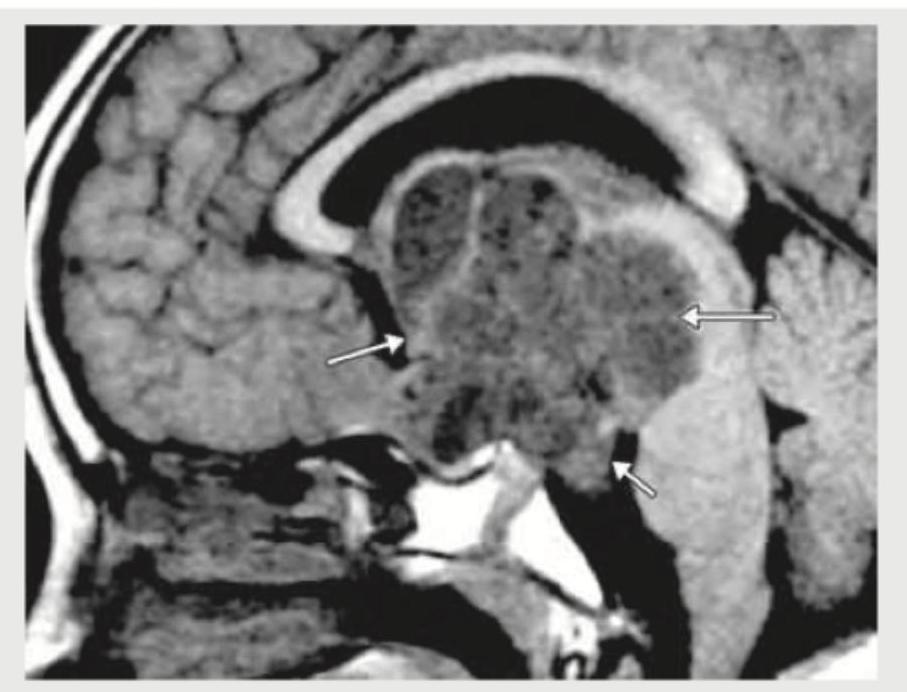

A 6 month infant was brought with complaints of a failure to gain weight and a large head. On examination, increased head circumference, bounding pulses and features of heart failure were noted. On cranial auscultation loud cranial bruit was heard. MRI head shows? (Recent NEET Pattern 2018-19)

Explanation: ***Vein of Galen formation*** - The clinical presentation of **failure to thrive**, **macrocephaly**, **bounding pulses**, **heart failure**, and a **loud cranial bruit** in an infant is highly characteristic of a **Vein of Galen malformation (VOGM)**. The image would show a dilated vein of Galen. - VOGMs are high-flow arteriovenous malformations that can lead to significant hemodynamic stress on the heart and hydrocephalus due to obstruction of CSF pathways. *Arachnoid cyst* - While arachnoid cysts can cause **macrocephaly** and, less commonly, obstructive hydrocephalus, they generally do not present with **heart failure**, **bounding pulses**, or a **cranial bruit**. - MRI would show a CSF-filled cyst that follows CSF signal on all sequences and typically does not enhance. *Arnold-Chiari malformation* - Arnold-Chiari malformations involve downward displacement of cerebellar tonsils or vermis through the foramen magnum and are associated with hydrocephalus, but they do not typically cause **heart failure**, **bounding pulses**, or a **cranial bruit**. - Clinical features usually relate to brain stem compression or hydrocephalus, such as apnea, stridor, or feeding difficulties. *Dandy-Walker syndrome* - Dandy-Walker syndrome is characterized by hypoplasia of the cerebellar vermis and cystic dilation of the fourth ventricle, often leading to **hydrocephalus** and **macrocephaly**. - However, it does not explain the **bounding pulses**, **heart failure**, or **cranial bruit** seen in this patient, which point to a vascular anomaly.